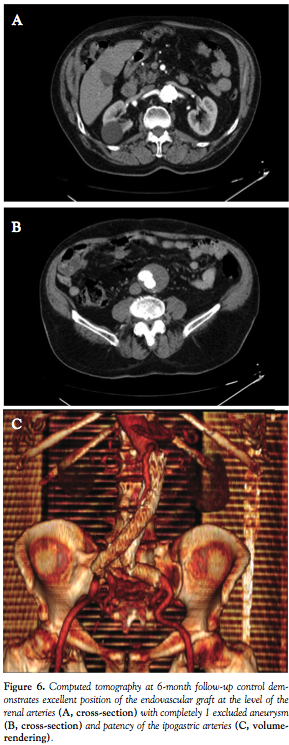

The procedure was then completed by deploying a 20 x 14 cm contralateral leg during inflation of a 34 mm tri-lobated balloon (W. L. Gore) in the EVG body at the level of the proximal stent edge, to stabilize the graft during contralateral sheet gate insertion, with a satisfactory final result (Figure 5). The patient was discharged two days after the procedure, and blood draws did not disclose any evidence of renal damage. Computed tomography demonstrated complete AAA exclusion without any endoleak at up to 6 months follow-up.